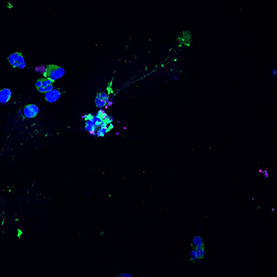

Many processes within the body are changed by the presence of cancer. These images show the response of microglia, immune defense cells in the brain, to cancer cells. When microglia encounter glioblastoma multiforme, one of the most aggressive brain cancers, they shift from a relaxed, elongated shape to a rounded, ready-for-combat conformation.

These images echo the work of Anna Atkins, a British botanist and photographer who used a contact printing technique called cyanotyping to capture the form of plants and algae. Emily Chen’s work similarly seeks to explore biological function, in this case the immune response to brain cancer, by capturing and comparing biological forms.